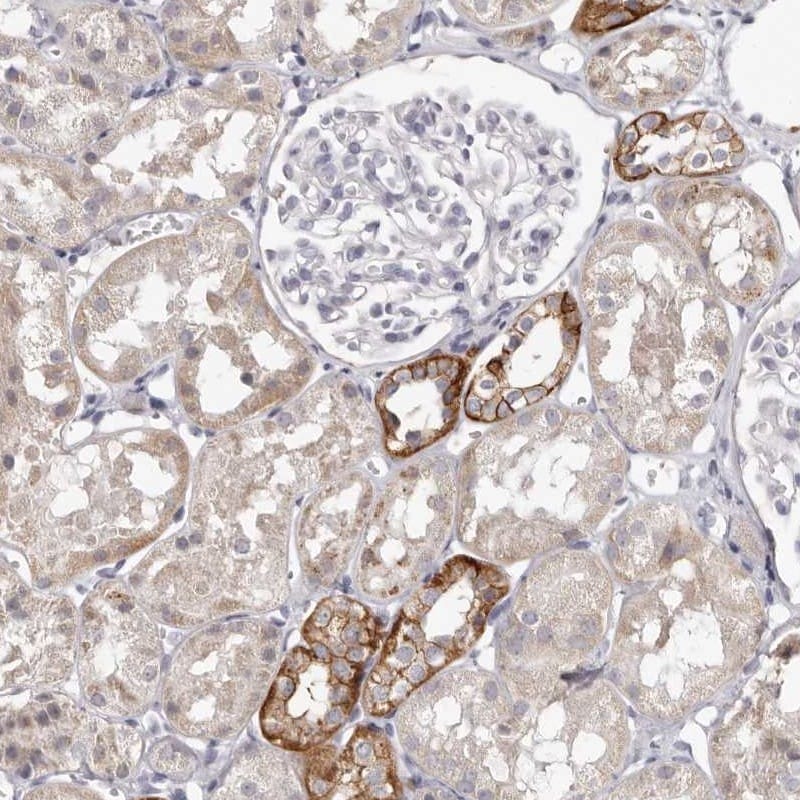

Supportive validation

- Submitted by

- Invitrogen Antibodies (provider)

- Main image

- Experimental details

- Immunohistochemical staining of PCDHB6 in human kidney using a PCDHB6 Polyclonal Antibody (Product # PA5-56192) shows strong cytoplasmic and membranous positivity in cells in tubules.